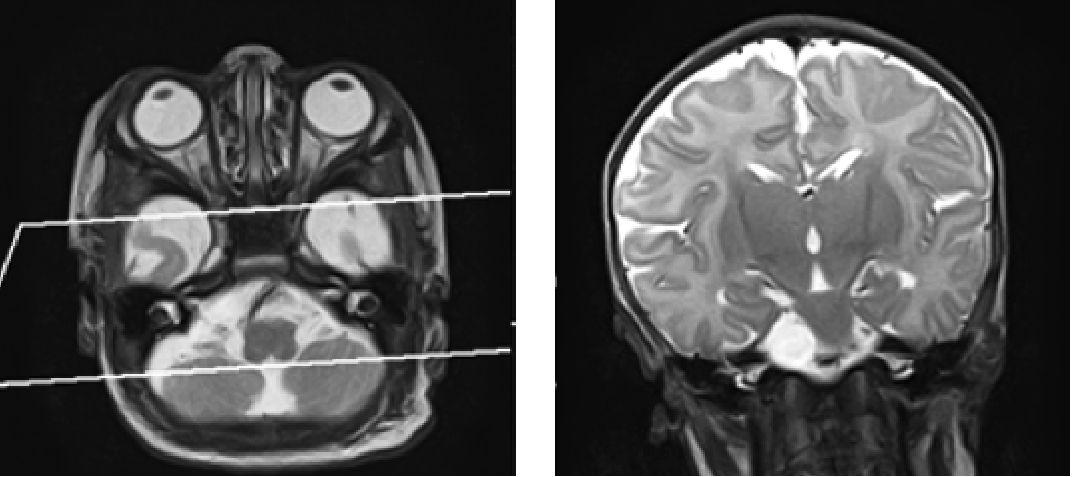

3. Коронарная проекция - по слуховым нервам (рис. 3).

Рис. 3. Пример позиционирования срезов по слуховым нервам аксиальной плоскости для получения изображения в коронарной проекции при проведении магнитно-резонансной томографии головного мозга на примере Т2 ВИ пациенту восьми месяцев жизни